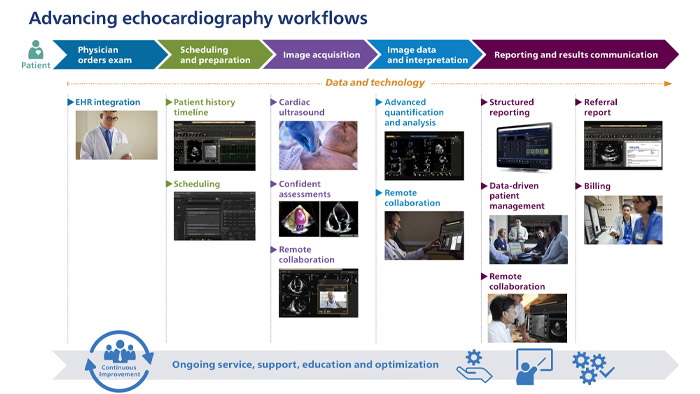

See how Philips intelligence is enabling care teams to work with enhanced efficiency throughout echocardiography from the time a physician orders the exam to study completion, billing and referral.

Streamline cross-functional workflow and collaboration among care givers

A single point of access to images and information anytime and virtually anywhere. Perform comprehensive analysis, quantification and reporting for fast, informed decision making.

Decrease deployment costs and save time while interfacing to existing systems through our zero footprint technology and interoperability.